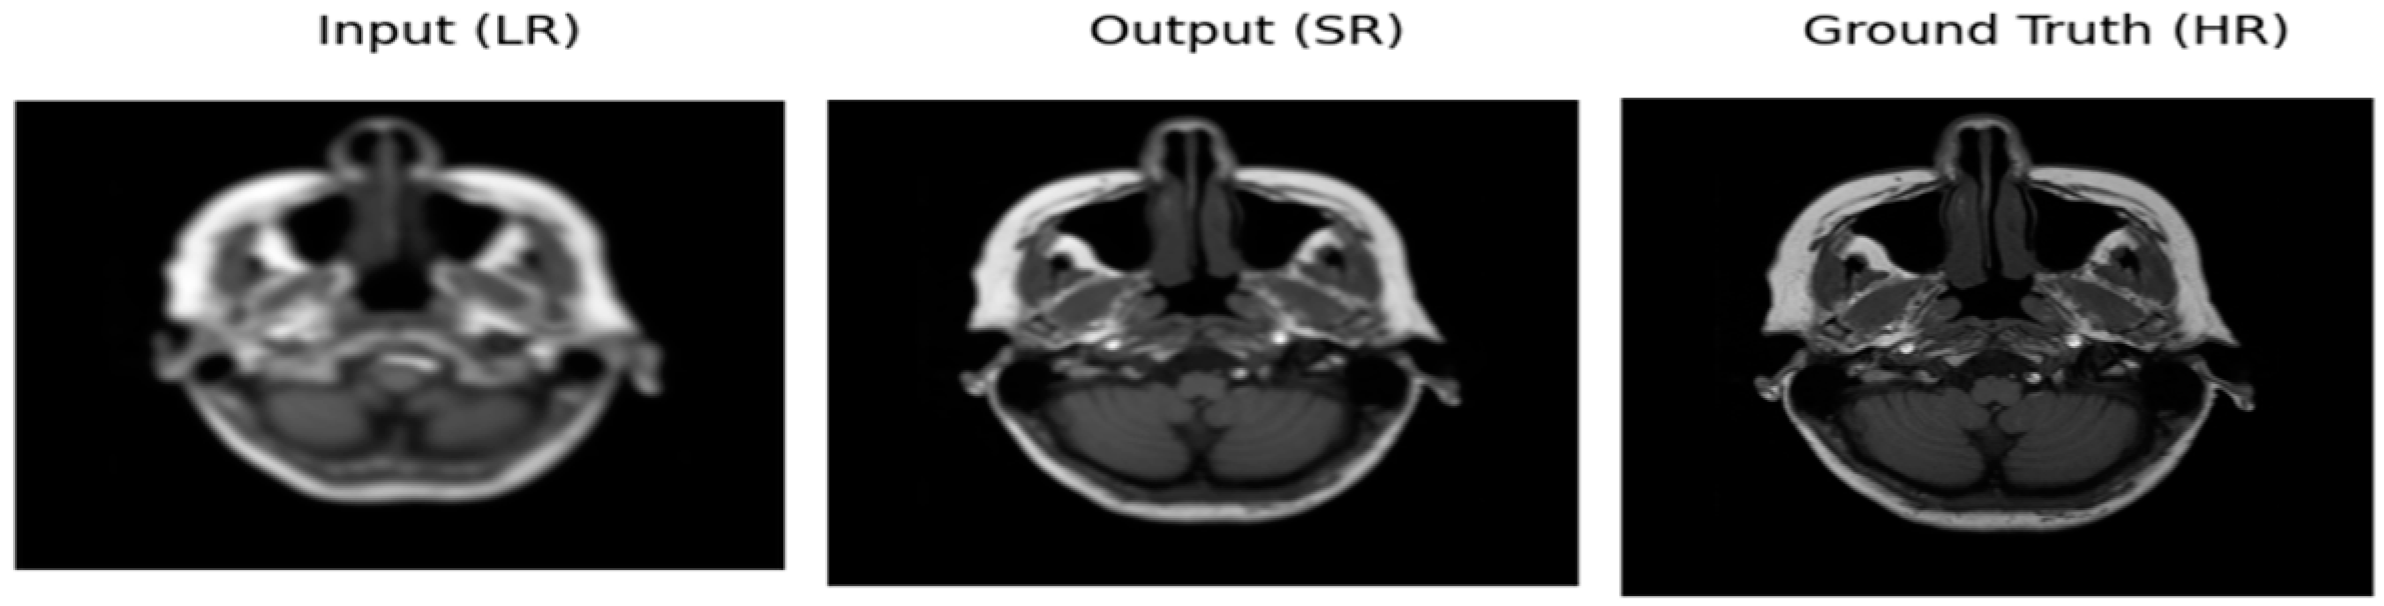

Resolution Enhancement of Brain MRI Images Using Deep Learning †

3.1. Qualitative and Quantitative Analysis